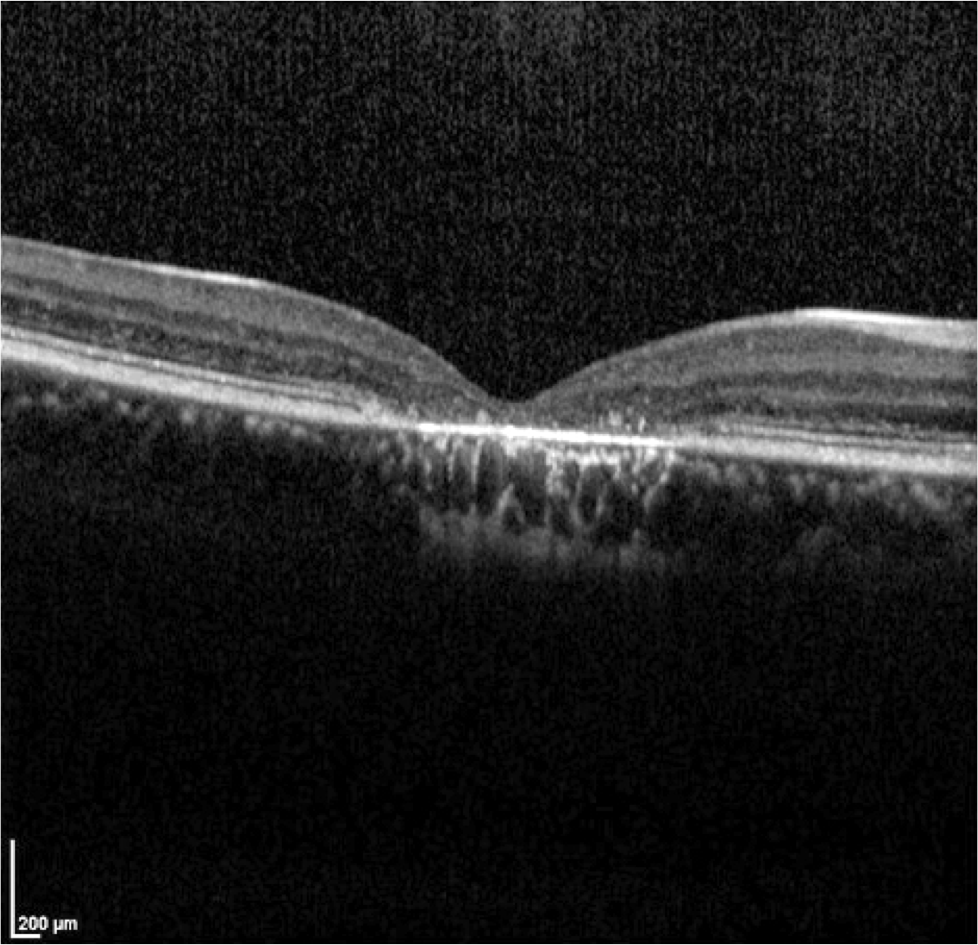

Case 10 is a 19 year old woman with 20/160 acuity. She had normal acuity as a child and both of her parents still have normal vision. She has moderately diminished color discrimination.

Optical coherence tomogram of the right eye.